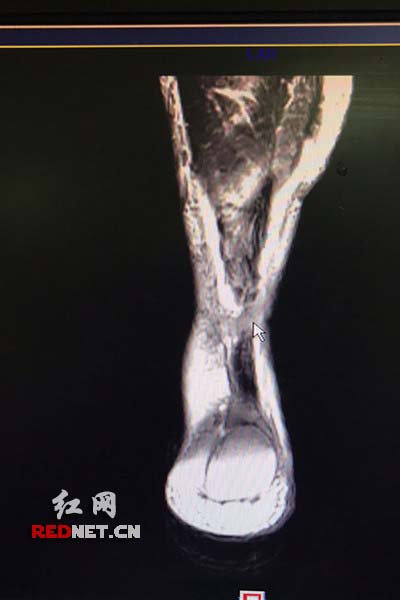

其它 跟腱断裂再损伤核磁共振图像

小鲁的核磁共振片显示,跟腱完全断裂(鼠标指示部位).